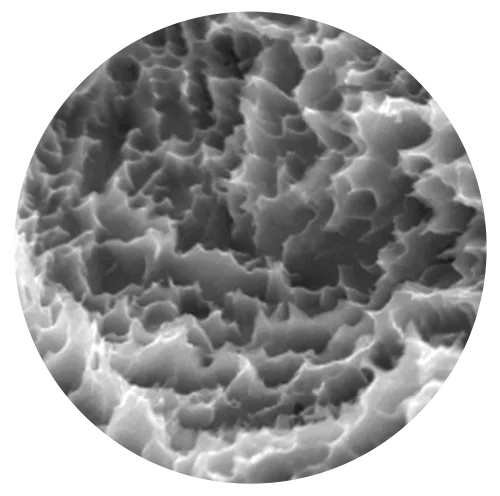

Tratamiento superficial Titansure Active y Titansure